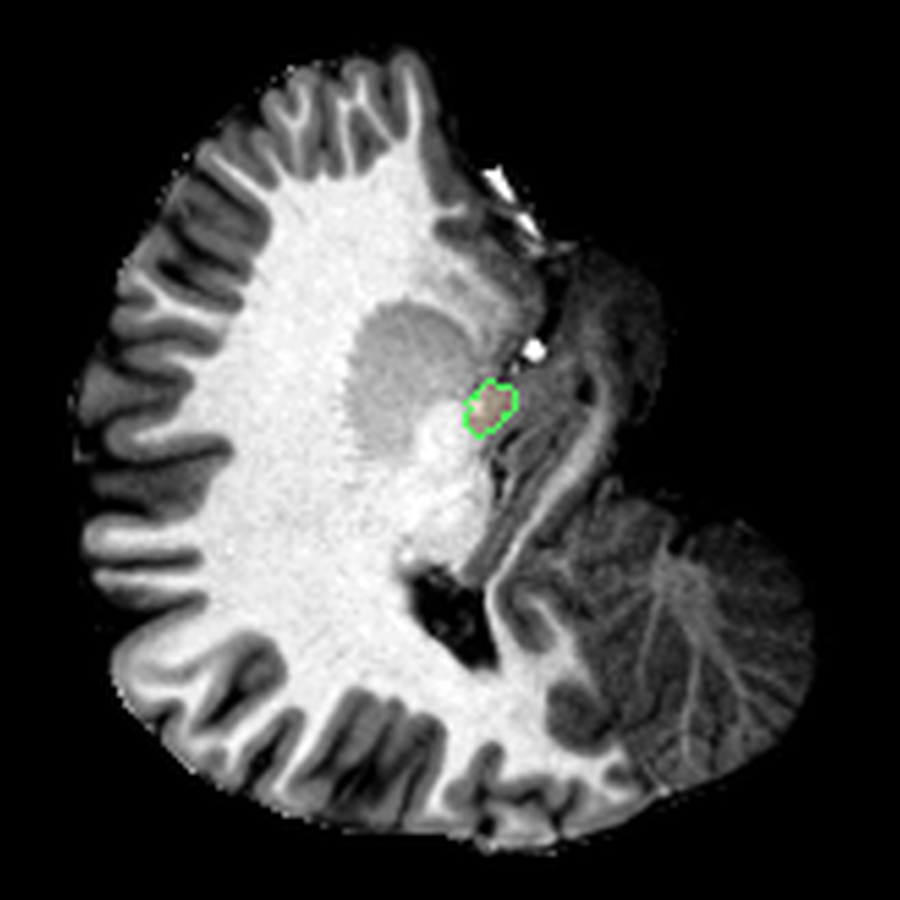

What I liked about having this data was that it changed how I interacted with the scan. Instead of staring at individual slices and guessing at the composition, I could start isolating specific parts of the brain.

The visualisations above show how little differentiation some brain regions have from their surroundings - I knew roughly where the thalamus was in the brain, but would never have been able to point it out on the MRI. At this stage, FreeSurfer plus some code had given me a perspective that would have been impossible for me to achieve myself.